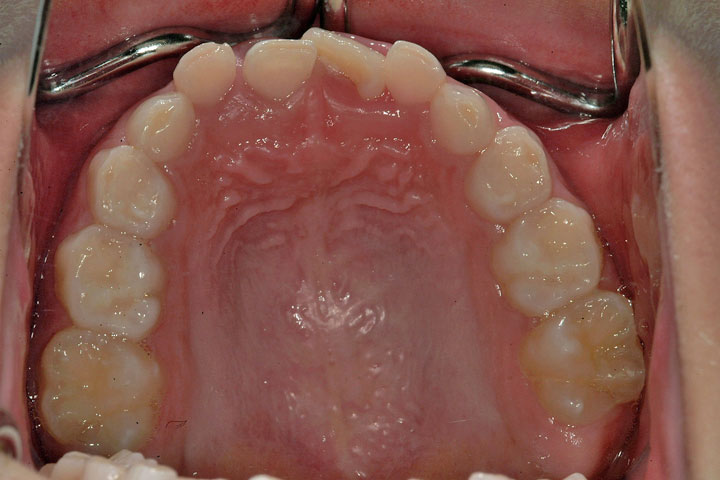

上下の前歯のデコボコを気にして来院された小学校1年生の男子です。上顎は装置で下顎はバイヘリックスで拡大を行い、その後は定期観察といたしました。永久歯交換後にデーモンシステムで最終的な配列を行っております。

症例画像

初診時

動的治療中

動的治療終了時